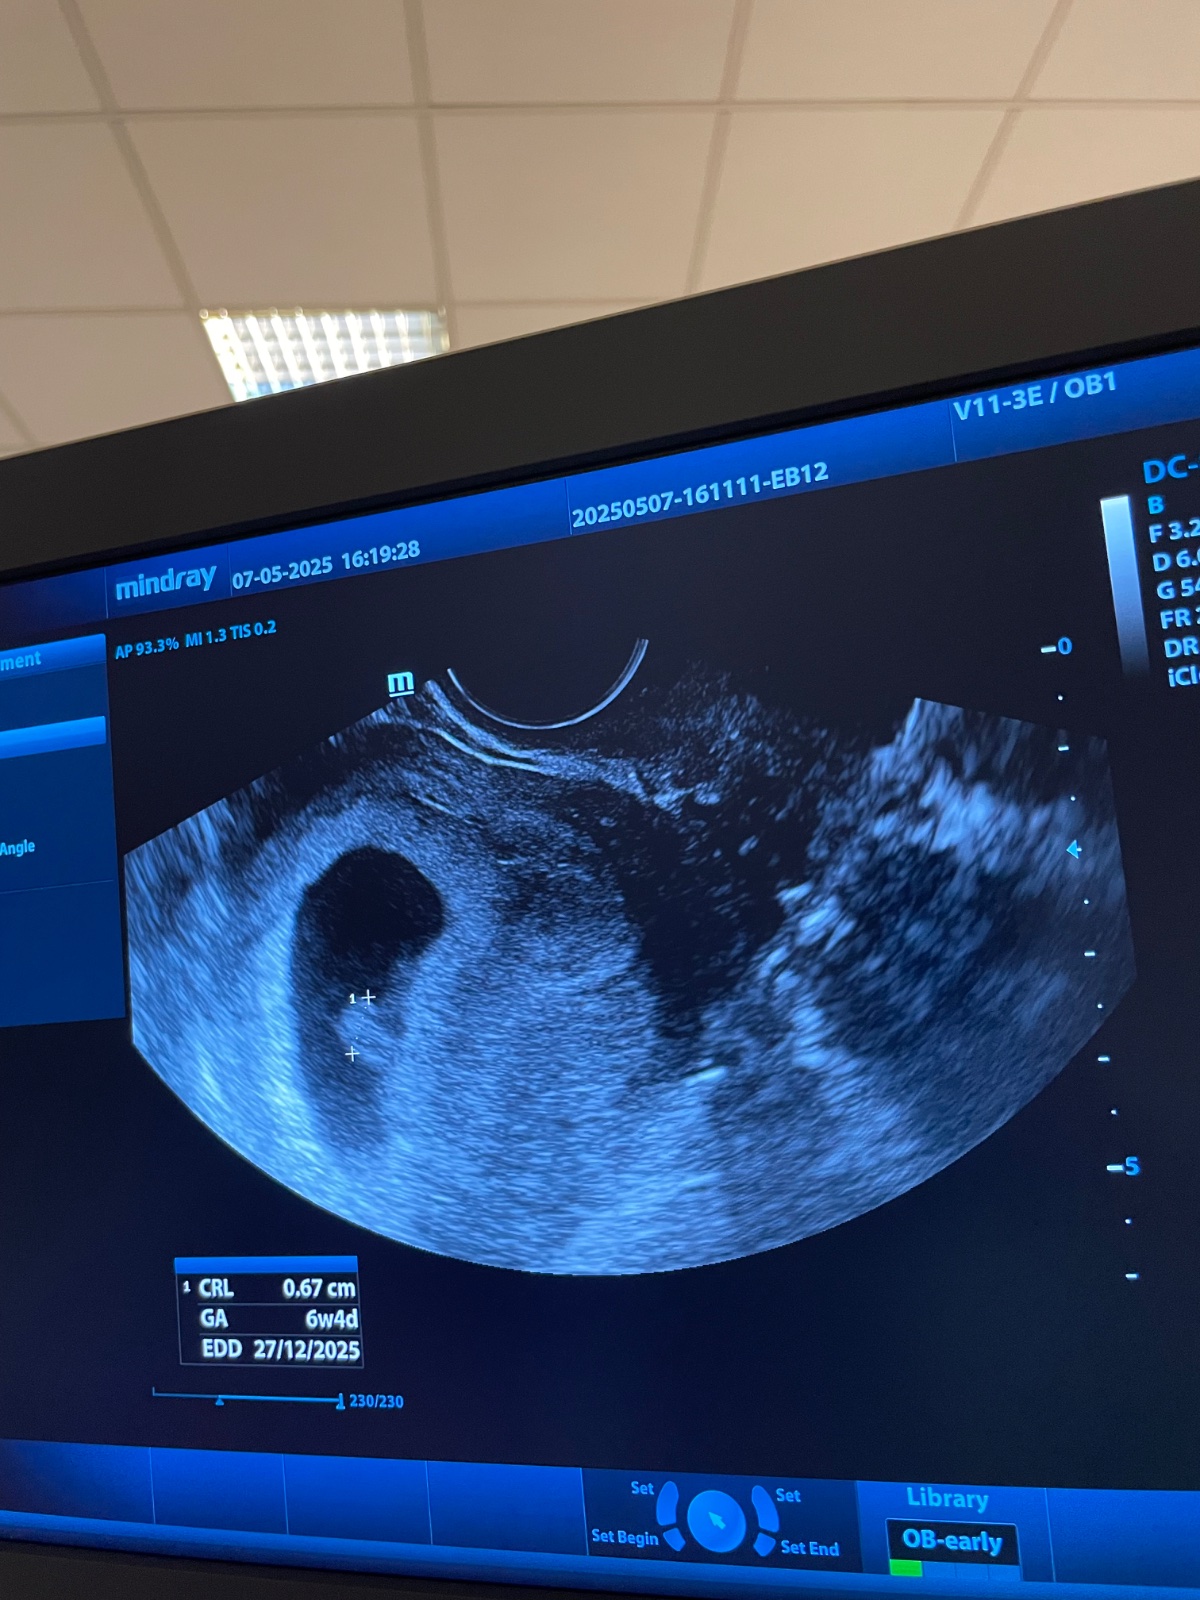

@majulka098 ahojteeee teraz som sa zastavila. V pistok ideme na svadbu tak sme boli nakupovať. Babatko je tam 🥹živé zdrave so srdiečkom. Uľavilo sa mi. Tt vychádzajú presne podľa poslednej poslednej ms aj sona. A ďalšia kontrola 28.5. Dali nám už aj tehotenskú knižku dokonca. Ďakujem ze ste na mna mysleli dievčatá 🩷

@zanzilady gratulujem z celého ♥️ veľa zdravia vám prajem obom….krásny aj termín pôrodu 😇 vianočný zázrak

@michicka dakujemeeee krásne 🥹🥹🥹anoooo vianočný alebo novoročný 😅od začiatku mi behá v hlave prvé babatko v roku 😂